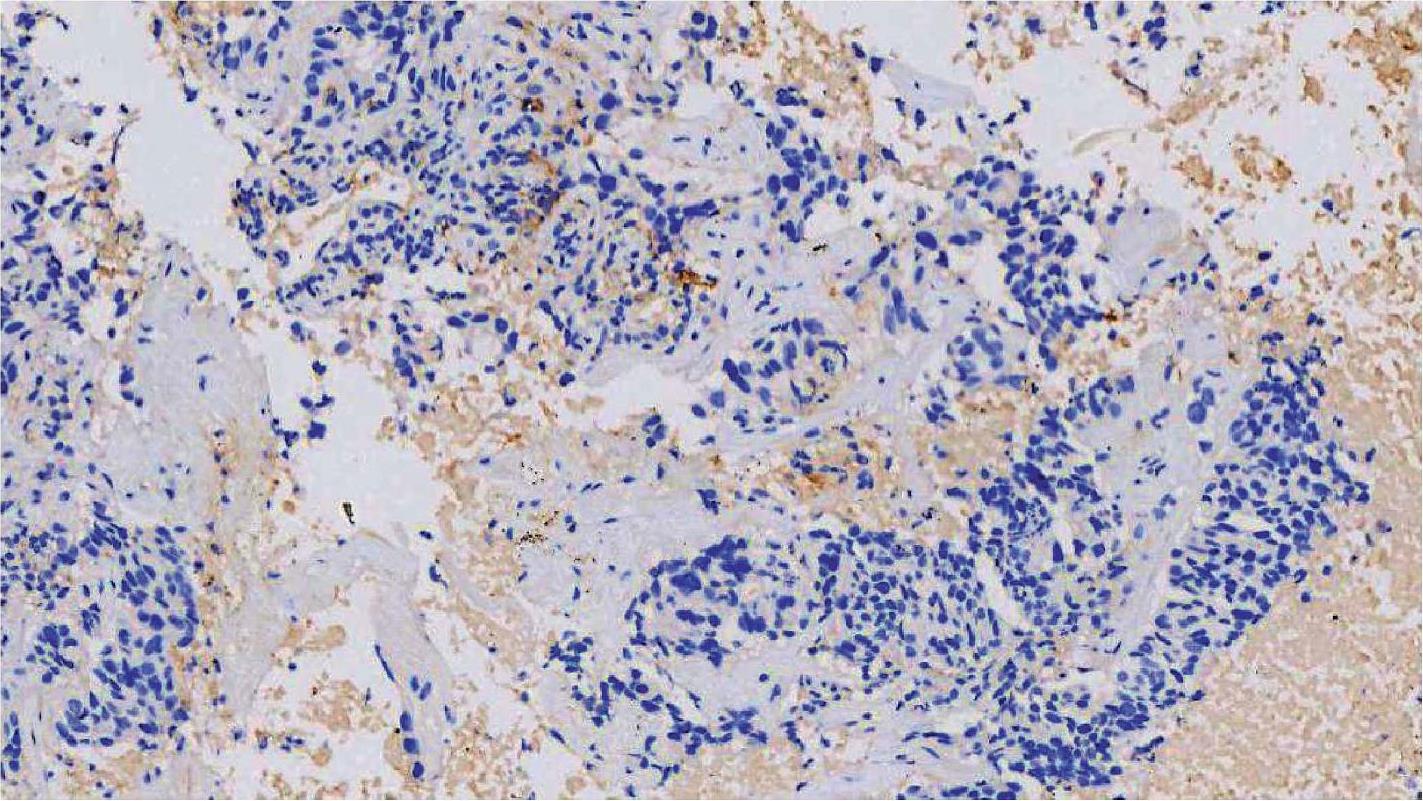

SP142克隆号的操作平台为罗氏诊断Ventana BenchMark Ultra。试剂盒配套完善,只需要灌注好大容量缓冲液及试剂,操作简单,做好质控结果同样稳定可靠,判读结果以TC和IC计算。具体评分时,TC、IC各采用4等级评分。其中TC膜染色4等级:0≤0级<1%、1%≤1级<5%、5%≤2级<50%、3级≥50%;IC染色也同样分为4等级:0≤0级<1%、1%≤1级<5%、5%≤2级<10%、3级≥10%。评分采用逐级评分步骤,先评估TC染色,若TC评分≥50%,则不必再评估IC;若TC评分<50%,则需要进一步评估IC染色。建议检测时TC和IC各自给出评分和(或)级别。TC评分0~3级的NSCLC PD-L1 (SP142)免疫组织化学染色结果分别如图2-18至图2-21所示。

图2-22 NSCLC PD-L1 (SP142)免疫组织化学染色图(×100),IC评分0级 [8]